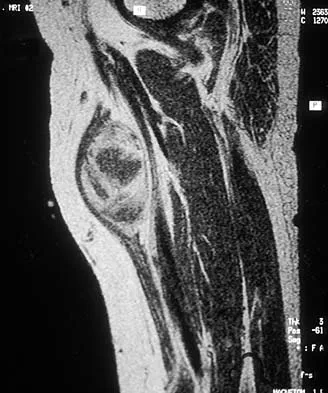

A 23-year-old man has had right posterolateral knee pain and occasional lateral calf dysesthesias for the past 8 months. A radiograph, CT scan, MRI scans, and a biopsy specimen are shown in Figures 62a through 62e. What is the most likely diagnosis?

Explanation:

The radiograph shows an eccentric, cortically based lytic lesion in the proximal fibula. The CT and MRI scans confirm that it is well circumscribed and cortically based with significant surrounding edema. The radiographic differential diagnosis would be a Brodie's abscess or osteoid osteoma. An osteoblastoma would have to be greater than 2 cm in size. A chondroblastoma may also have significant edema around it, but it is an epiphyseal-based lesion, not cortically based. The well-circumscribed nature of the lesion is not consistent with osteosarcoma. The pathology shows a very cellular and vascular stroma with plump, but not atypical osteoblast cells making a matrix of immature woven bone. There are no abundant inflammatory cells or dead bone suggestive of osteomyelitis or a Brodie's abscess. Therefore, the clinical and histologic picture is most consistent with an osteoid osteoma. Percutaneous radiofrequency ablation, usually with CT guidance, has become the preferred method for treating most cases of osteoid osteoma. Rosenthal DI: Radiofrequency treatment. Orthop Clin North Am 2006;37:475-484.